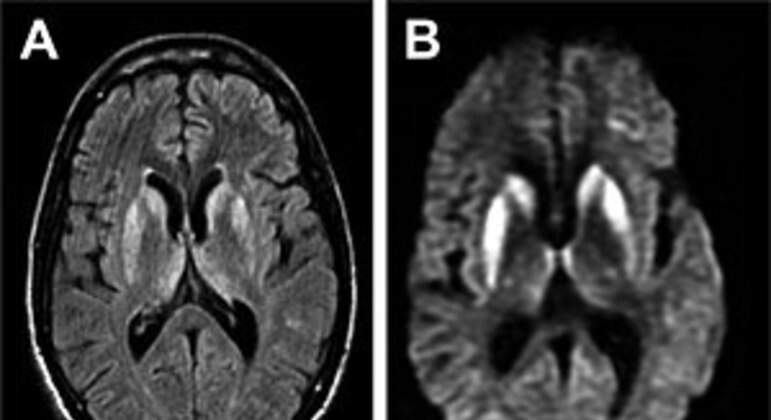

Horas após confirmar que dois pacientes estavam internados no Rio de Janeiro com suspeita de EEB (encefalopatia espongiforme bovina), conhecida popularmente como “doença da vaca louca”, o INI/Fiocruz (Instituto Nacional de Infectologia Evandro Chagas/Fundação Oswaldo Cruz) descartou a hipótese de que os casos tenham relação com o consumo de carne contaminada.

Em nota, o vice-diretor de serviços clínicos da instituição, Estevão Portela Nunes, afirma que, “considerando os aspectos clínicos e radiológicos”, os casos estão sendo tratados como “suspeita da forma esporádica da doença de Creutzfeldt-Jakob”.

De acordo com o Manual MSD de Diagnóstico e Tratamento, a DCJ (doença de Creutzfeldt-Jakob) também é uma encefalopatia espongiforme, mas mais comum do que a doença da vaca louca.

A forma esporádica é, segundo o guia, o tipo mais comum, representando 85% de todos os casos. “A DCJ esporádica geralmente afeta pessoas com mais de 40 anos de idade (média etária de cerca de 65 anos).” A doença da vaca louca é classificada como a forma adquirida.

As duas são doenças neurodegenerativas raras e denominadas priônicas, por serem causadas por príons – formas modificadas de uma proteína presente normalmente no organismo.